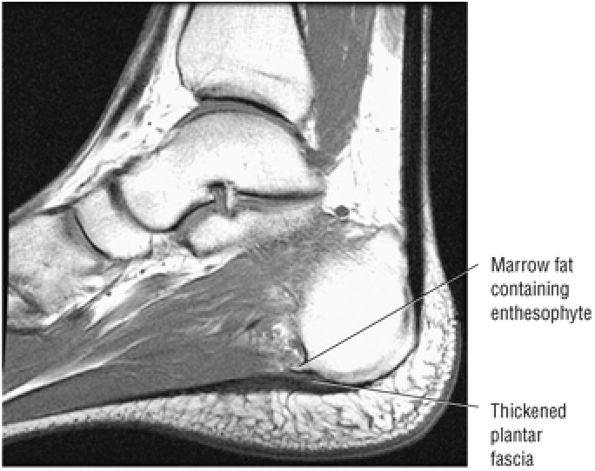

Enthesopathic insertional tendinitis (Fig. 5.114)

Haglund's deformity (Figs. 5.115, 5.116, and 5.117) (insertional tendinitis with reactive calcaneal marrow edema [see Fig. 5.116], and the constellation of thickened tendon, retrocalcaneal/tendo Achilles bursitis, and a calcaneal bony prominence)

Hypertrophic spurring or enthesophytes